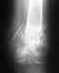

Добрый день!!! Играл в футбол! Упал на правое плечо и на половину разорвал половину связки которая держит ключицу (акромиальная связка), это по результатам узи, ключица на 1-1,5 см поднята и торчит в плече, как лучше поступить?